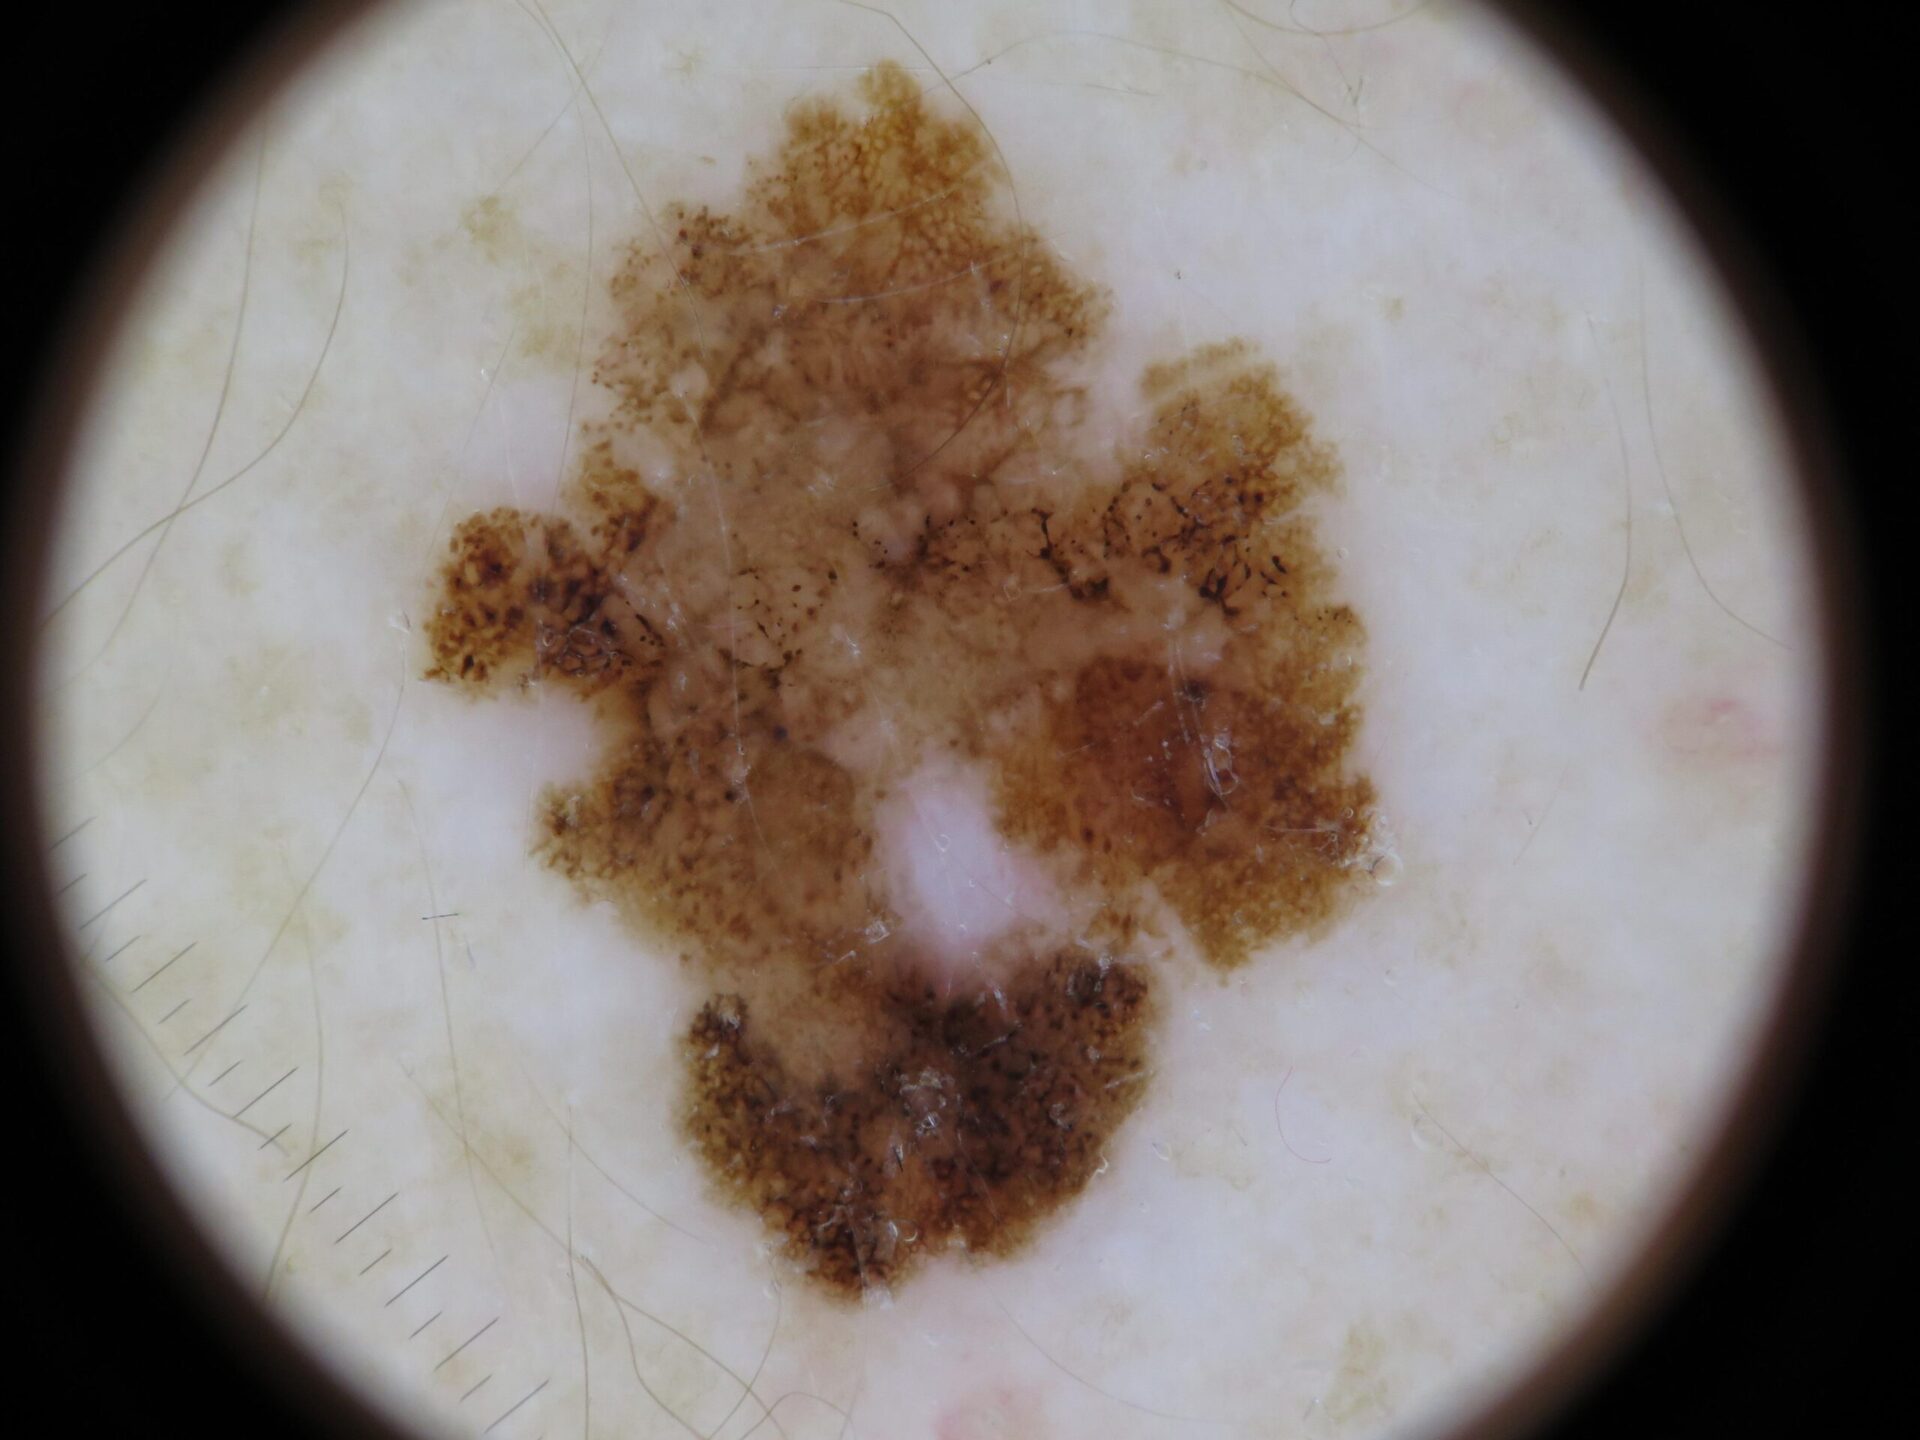

Actinic keratosis on posterior torso. Photo: International Skin Imaging Collaboration at isic-archive.com